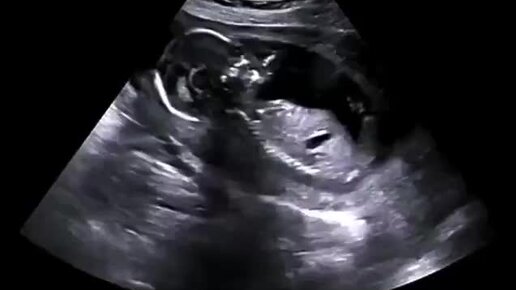

Вот что происходит с ребёнком когда мама смеëтся🤣🐣